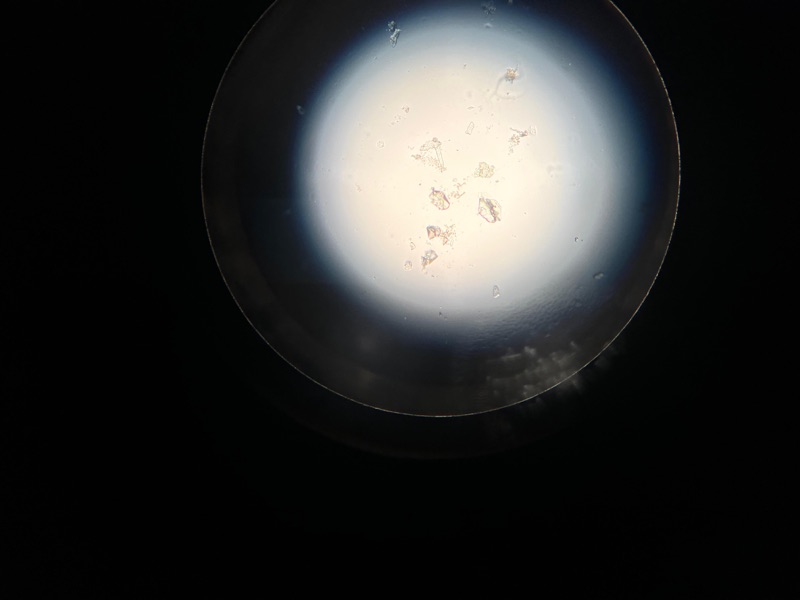

妹豬睇醫生 Get link Facebook X Pinterest Email Other Apps March 29, 2026 由於妹豬忍尿問題已有一段時日,星期六帶妹豬的尿去驗,夜間獲通知有晶石,所以星期日需帶妹豬去檢查!蔽日帶妹豬去診所照X光,萬幸無結石,只需食藥,但將來要留意骨刺的問題 Get link Facebook X Pinterest Email Other Apps Comments